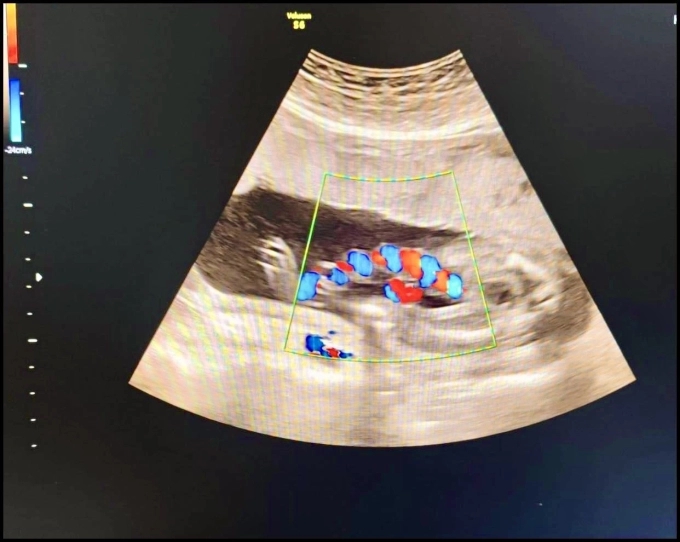

Sau khi thăm khám và làm các cận lâm sàng cần thiết, kết quả cho thấy: qua siêu âm có hình ảnh xoắn dây rốn; qua theo dõi tim thai liên tục bằng Monitoring sản khoa phát hiện tim thai giảm đột ngột nên các bác sĩ đã nhanh chóng tiến hành hội chẩn và mổ lấy thai khẩn cấp.

BSCKI. Đặng Thị Việt Phương, Trưởng Khoa Sản là người trực tiếp phẫu thuật cho sản phụ cho biết: Trường hợp này rất hiếm gặp vì dây rốn xoắn nhiều vòng liên tiếp và sát nhau, đoạn xoắn liên tục và vị trí dây rốn bị xoắn lại tiếp xúc ngay sát bụng thai nhi. Nếu không kịp thời được phẫu thuật thì trẻ có thể bị suy hô hấp và ảnh hưởng đến sức khỏe.